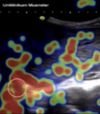

Medical Education

Medicine is a visual discipline! A central aspect of our work is therefore the analysis of eye movements to better understand how we look at medical images (e.g., histological sections or sonoanatomical images). By using various eye-tracking technologies (including "webcam-based" ... [ mehr ].